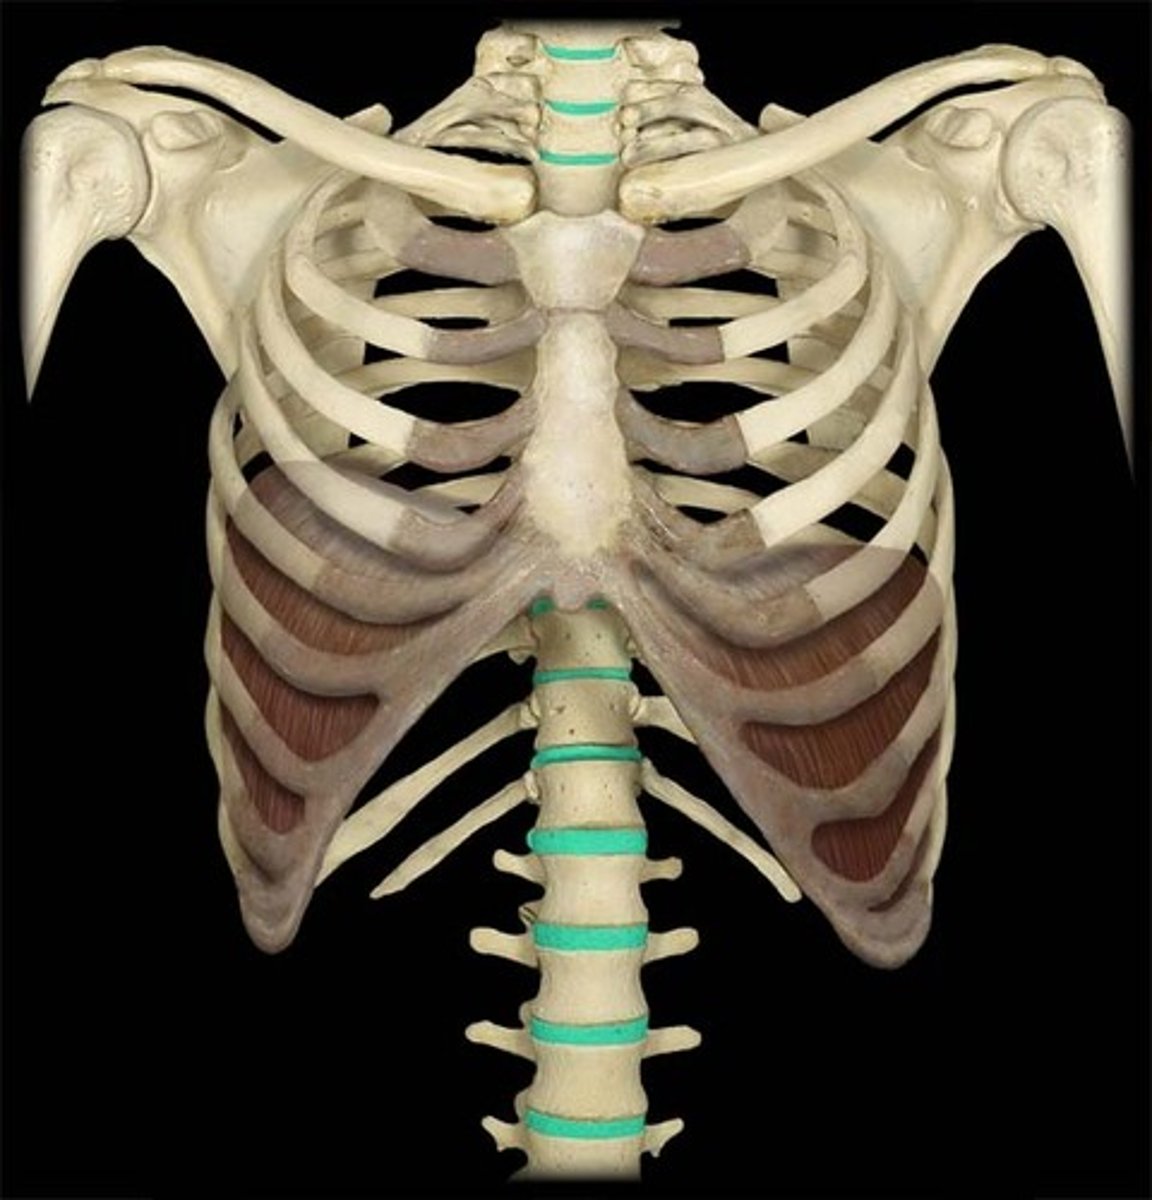

What are the sections of the vertebral column?

cervical, thoracic, lumbar, sacrum, coccyx

How many vertebrae make up the thoracic spine?

12

What is the unique characteristic of the thoracic spine?

facets for rib articulation